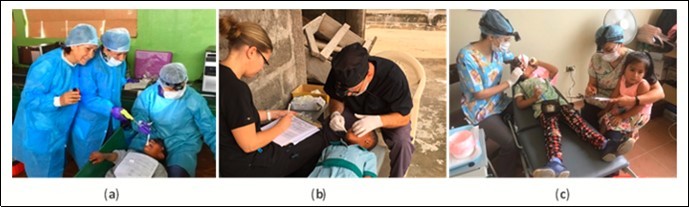

All patients received comprehensive instructions on promoting healthy food choices and good oral hygiene practices. Toothbrushes were donated to all of the participating schools to help maintain good oral health. Examples of clinical treatment settings in Ecuador, Ghana and Bolivia can be seen in Figure 1. No removal of caries lesion tissue was conducted before application of 50% SN or 38% SDF followed by FV in any of the humanitarian projects. Removal of decayed tooth structure before treatment using silver ion compounds does not increase the caries lesion arrest rate.11,16 All children were instructed to not eat or drink for at least one hour after treatment and to not brush their teeth until the next day.

Figure 1.Examples of children being treated in Ecuador (a), Ghana (b), and Bolivia (c).